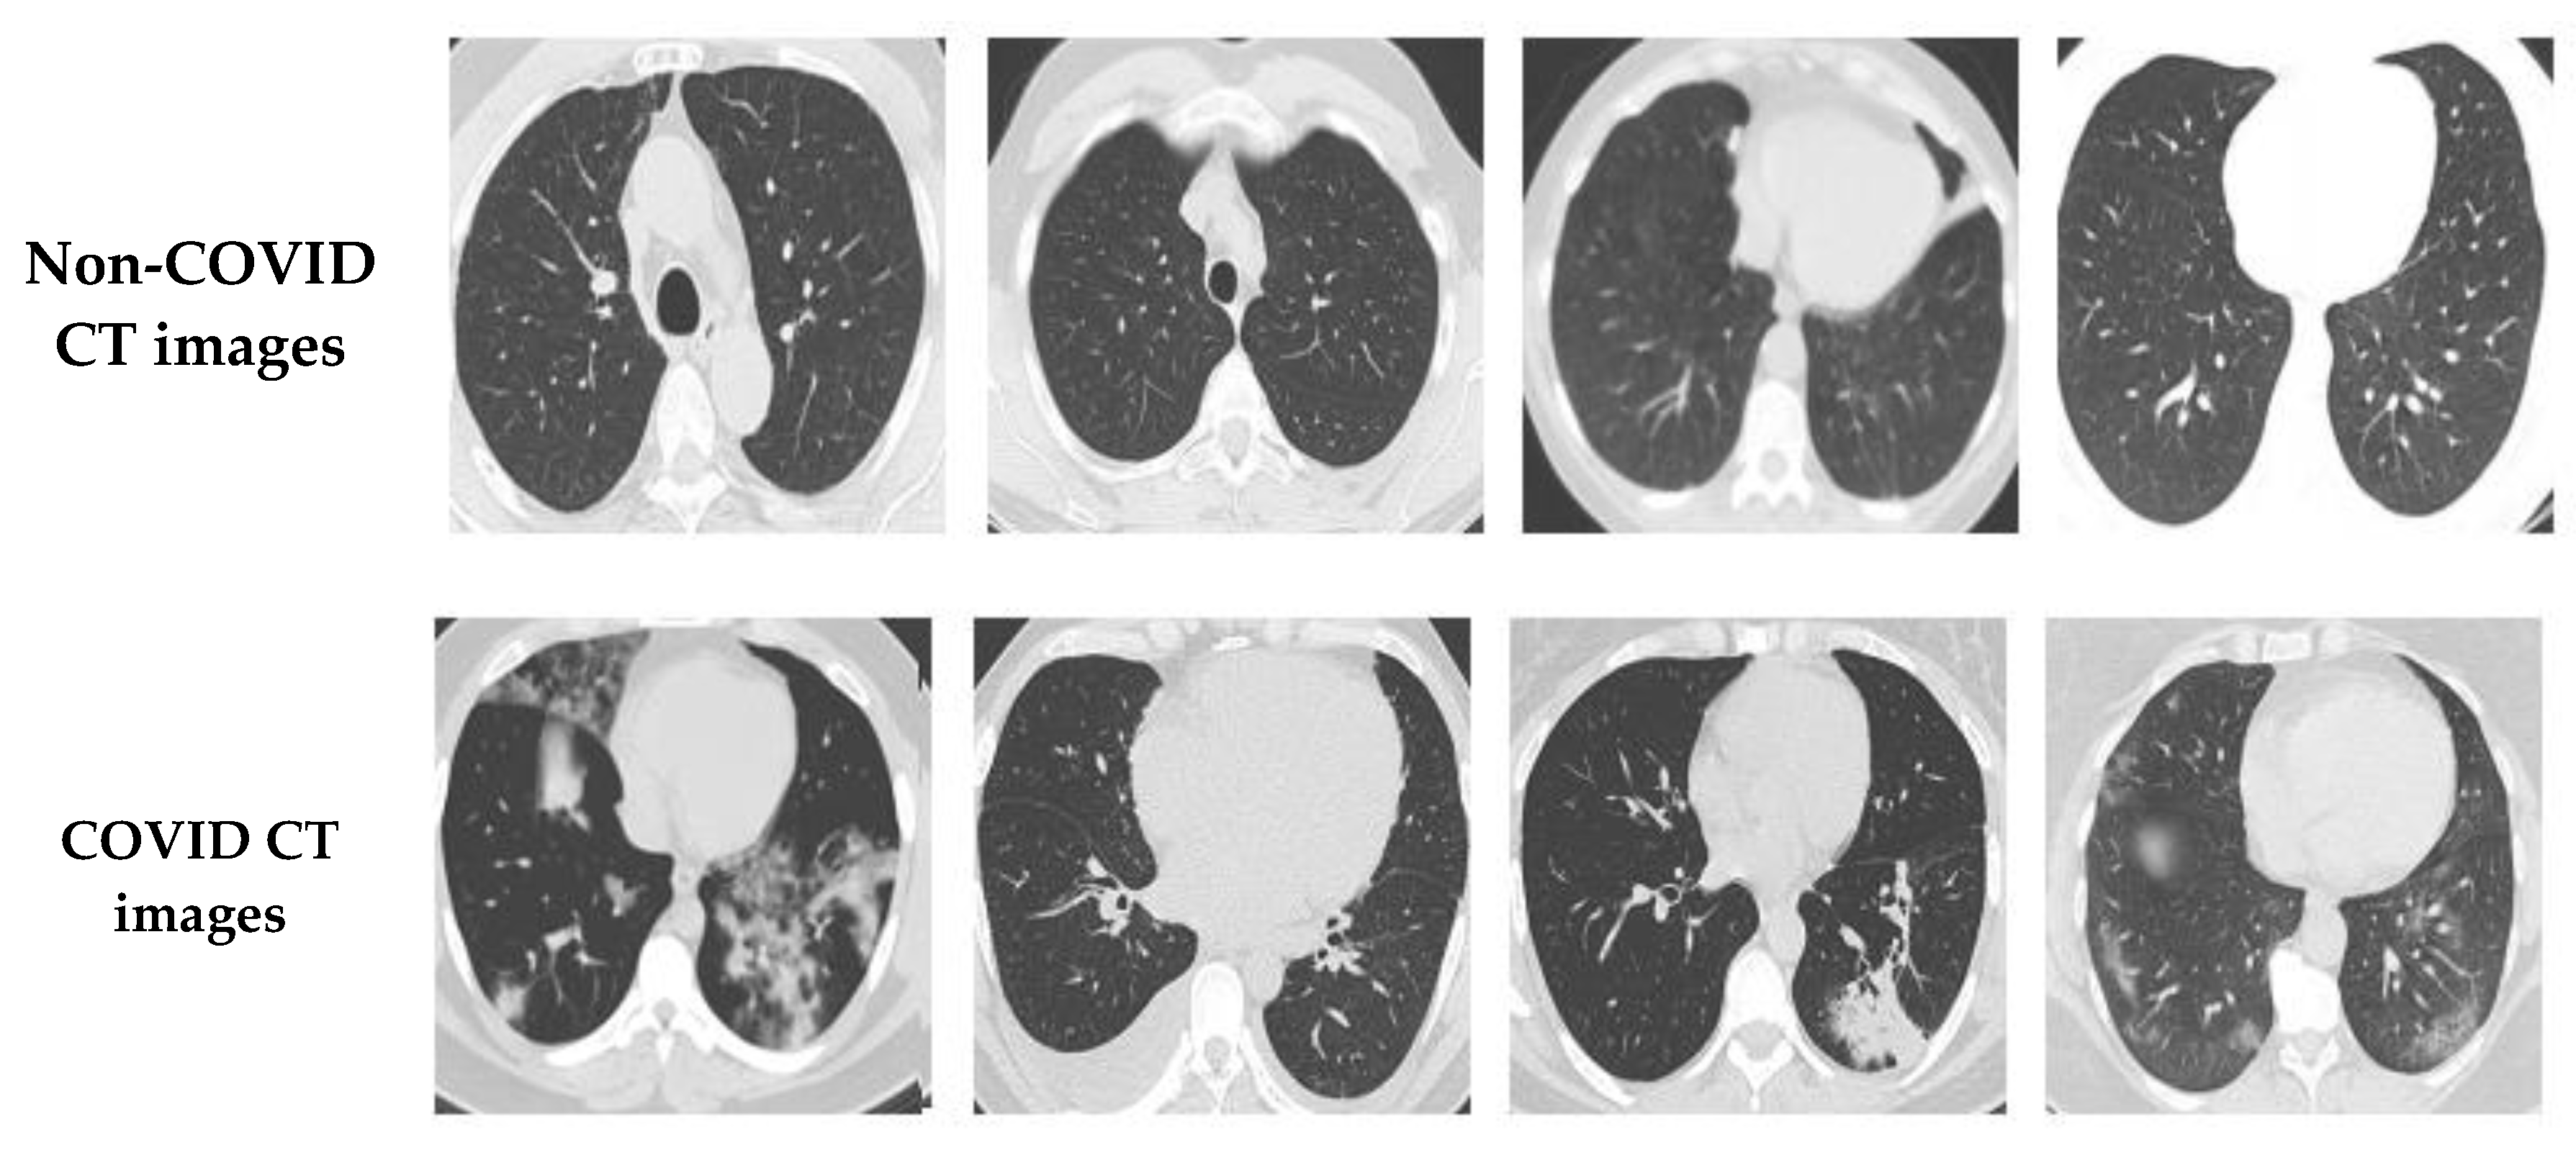

In this study, two different open-access sources were used as our basic experimental datasets. The CT scan dataset [34] had a total number of 2481 CT images divided into 1229 normal cases and 1252 COVID-19 patients, whereas the chest X-ray dataset [35] had 6939 sample images consisting of three classes (COVID-19, normal, and pneumonia), with 2313 samples used for each category. Figure 6 shows samples from the CT scan dataset and Figure 7 shows samples from the chest X-ray dataset. Next, the database was split into training and testing sets. The details for the training and testing samples are shown in Table 1 and Table 2 for the CT scan and chest X-ray datasets, respectively, with the results of the different models displayed in the subsequent tables. Table 1 describes the splitting strategy used for the training and testing sets in the experiment for the CT scan dataset. The 80–20 training–testing ratio was adopted in our experiments. The COVID-19 class had 1013 images for training and 239 images for testing, while the normal class had 971 images for training and 258 for the testing set. Table 2 describes the splitting strategy used for the chest X-ray dataset. This dataset had an equal distribution, with 1850 images for training and 463 images for testing in each class. Data augmentation techniques were employed here to effectively increase the number of training samples. The images were augmented through cropping, noising, brightness modifications, contrast modifications, and random flipping.

Figure 6.

Sample COVID-19 and non-COVID CT images.